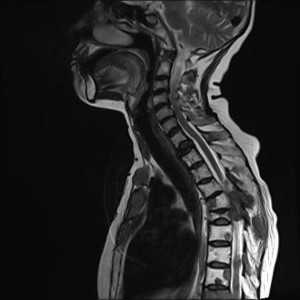

Стандартный протокол МРТ исследования позвоночника при подозрении на метастатическое поражение состоит из Т1-зависимых сагиттальных МРТ позвоночника и Т2-зависимых МРТ с подавлением сигнала от жира. Литические метастазы замещая костный мозг выглядят гипоинтенсивными на Т1-зависимых МРТ. На Т2-зависимых МРТ позвоночника они могут быть гипоинтенсивными, изоинтенсивными, если они склеротические, либо яркими, если они литические, особенно при подавлении сигнала от жира. Метастаз может диффузно поражать костный мозг позвонка или быть очаговым. На самой ранней стадии диффузного поражения заметно исчезновение сигнала при МРТ позвоночника от вертебробазилярной вены, процесс захватывает ножки дуг и задние структуры позвонка. Параспинальное распространение лучше видно на Т1-зависимых коронарных МРТ срезах, а компрессия спинного мозга на сагиттальных МРТ. На последнем этапе желательны контрастированные Т1-зависимые МРТ позвоночника в сагиттальной и поперечной плоскостях. Чувствительность МРТ превышает 90%, что заметно превосходит радионуклидную диагностику. В плане дифференциации метастазов и доброкачественных заболеваний МРТ не абсолютно надежна. Дифференциальная диагностика с гематологической патологией – плазмоцитомой, лимфомой и лейкозами практически невозможна и требует аспирационной биопсии. Реакцией костного мозга, напоминающей метастатическое поражение, сопровождаются доброкачественные переломы. Однако сигнал при МРТ позвоночника выражено неоднородный, задние структуры и костный мозг в заднем отделе тела позвонка остаются интактными. Более надёжным в плане дифференциальной диагностики является использование диффузионно-взвешенных МРТ. При доброкачественном переломе через 1 – 3 месяца сигнал возвращается к норме.

МРТ позвоночника. Сагиттальная Т1-зависимая МРТ. Множественные метастазы в позвоночник.

МРТ позвоночника. Сагиттальная Т2-зависимая МРТ. Множественные метастазы в позвоночник.